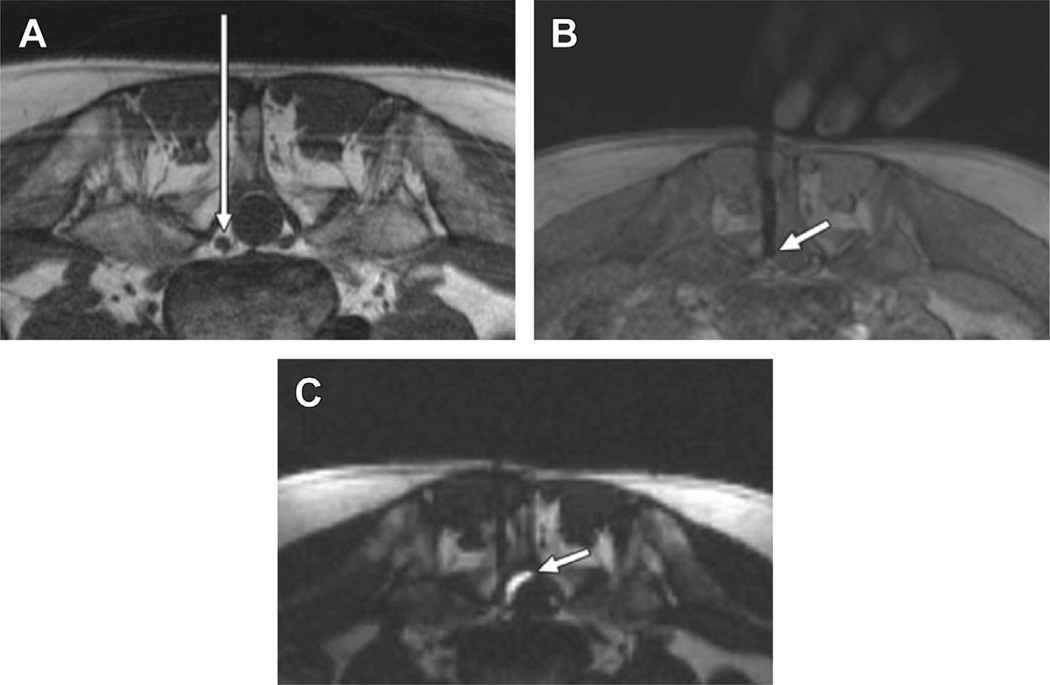

Fig. 2.

MR imaging–guided injection of steroid into lumbar facet joint. (A) Axial T1-weighted turbo spin echo MR image shows planned needle path (long arrow) for steroid injection of the right L4–L5 facet joint (short arrow). (B) FLASH two-dimensional MR imaging allows real-time visualization during advancement of needle (arrow) to facet joint. (C) Axial fat-saturated T1-weighted turbo spin echo MR image acquired after injection of 0.8 mL of steroid and gadolinium-based contrast mixture demonstrates injectant (arrow) in joint space. (From Fritz J, Thomas C, Clasen S, et al. Freehand real-time MRI-guided lumbar spinal injection procedures at 1.5 T: feasibility, accuracy, and safety. AJR Am J Roentgenol 2009;192:W164; with permission.)